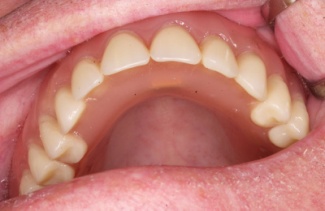

Klasickým příkladem a indikací pro použití implantátu je ztráta jednoho zubu (v tomto případě v předním – frontálním úseku) v jinak zdravém, nepoškozeném chrupu.

Nejčastější příčinou takové ztráty je sportovní nebo dopravní úraz.

Náhrada jednoho zubu pomocí implantátu je možná také v postranním úseku chrupu. Při ztrátě většího počtu zubů ve frontálním nebo postranním úseku může být mezer uzavřena větším počtem jednotlivých implantátů.

Při ošetření pomocí jednotlivých implantátů zůstávají sousední zuby neporušené – intaktní. Při klasickém ošetření pomocí můstků musejí být tyto zuby obroušeny!